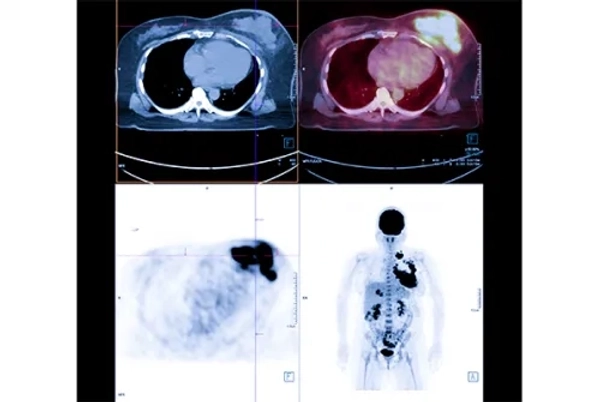

Diagnosis in Neuroendocrine Tumors: Advanced PET/CT Technology

Conventional imaging methods may not always be sufficient for diagnosing neuroendocrine tumors. For this reason, Gallium-68 DOTATATE PET/CT, performed with specialized smart molecules, is currently one of the most effective diagnostic methods.

Thanks to this advanced technology, tumors are detected at the molecular level, allowing the location and extent of the disease to be determined with much greater precision.